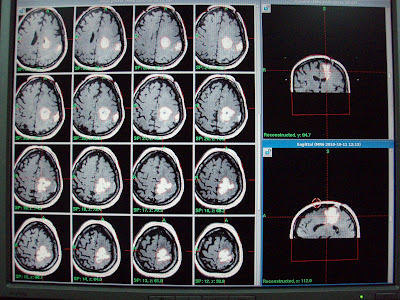

METHODS: In total, 72 patients (PD characterized by tremor, n = 59; ET, n = 13) were registered at 6 Japanese institutions. Following our selective thalamotomy procedure, the lateral part of the ventralis intermedius nucleus, 45% of the thalamic length from the anterior tip, was selected as the GK isocenter. A single 130-Gy shot was applied using a 4-mm collimator. Evaluation included neurological examination, magnetic resonance imaging and/or computerized tomography, the unified Parkinson's disease rating scale (UPDRS), electromyography, medication change, and video observations.

RESULTS: Final clinical effects were favorable. Of 53 patients who completed 24 months of follow-up, 43 were evaluated as having excellent or good results (81.1%). UPDRS scores showed tremor improvement (parts II and III). Thalamic lesion size fluctuated but converged to either an almost spherical shape (65.6%), a sphere with streaking (23.4%), or an extended high-signal zone (10.9%). No permanent clinical complications were observed.